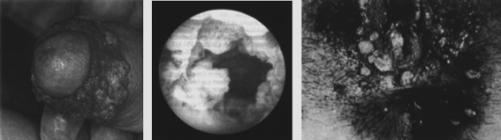

Vengono

illustrati i seguenti stadi:

1.9.2 Sifilide

II stadio: torace

1.9.3 Sifilide

II stadio: pianta dei piedi

1.9.4 Sifilide

III stadio: malleoli

1.9.1 Sifilide I stadio

1.9.2 Sifilide II

stadio: torace

1.9.3 Sifilide II

stadio: palmo dei piedi

1.9.4 Sifilide III

stadio: malleoli

1.9 Sifilide

Infezione

cronica con batt. Treponema pallidum.

Incubazione:

1ä3 settimane.

Infezione:

normalmente sessuale, raramente in micro-ferite.

Diagnosi:

test ematico specifico (Wassermann).

Divulgazione:

mondiale (ca. 20 milioni di infettati, 1 su 300).

Evoluzione:

- I stadio: 1ä3 settimane per 2ä4

settimane: prima incubazione: nodulo infiammato non doloroso che si decompone

su genitali (raramente altri posti) e persiste ev. per mesi. I germi si

divulgano tramite linfa/sangue.

- II stadio: ä10 settimane dopo l¼infezione

per 2ä3 anni: incubazione secondaria: gonfiore di noduli linfatici generali,

febbre, mal di testa/articolazioni. Eczema „maculoso¾ poi papuloso (non prude

ma doloroso a pressione), ev. placche orali e perdita di capelli irregolare.

Facilmente da confondere con malattie dermiche: diagnosi sierologica!

- III stadio: 3ä5 anni. Diventato raro

perchÈ trattamento antibiotico in stadio I/II: „gonfiori granulomatosi¾ negli

organi pi˜ diversi, p.es. faccia, cervello, cuore, fegato, rene, muscoli, ossa,

aortaä

- IV stadio: 10...20 anni: neurosifilide

con tabes dorsalis e paralisi progressiva.